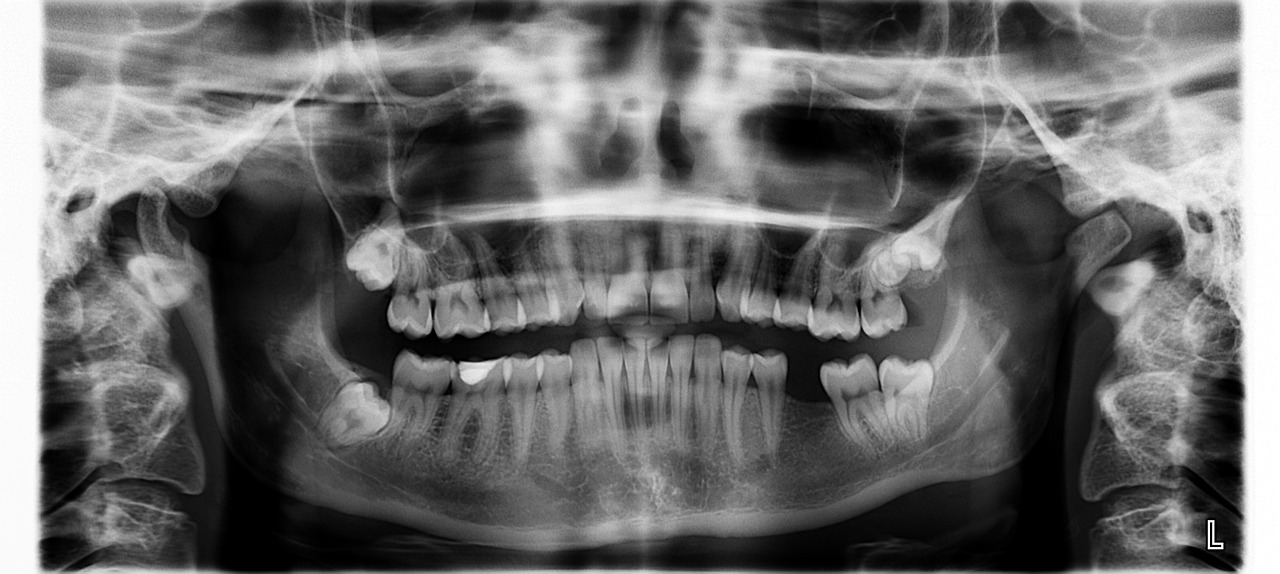

치아가 쉽게 깨지는 증상이 생긴다면

당뇨병 환자는 면역력이 저하되어 감염에 취약해지며, 구강 건강에도 영향을 미칠 수 있습니다. 치아가 쉽게 깨지거나 잇몸이 붓고 출혈이 발생하는 경우, 이는 당뇨병으로 인한 구강 합병증일 수 있습니다. 당뇨병 환자는 구강 위생을 철저히 관리해야 하며, 정기적인 치과 검진이 필요합니다.